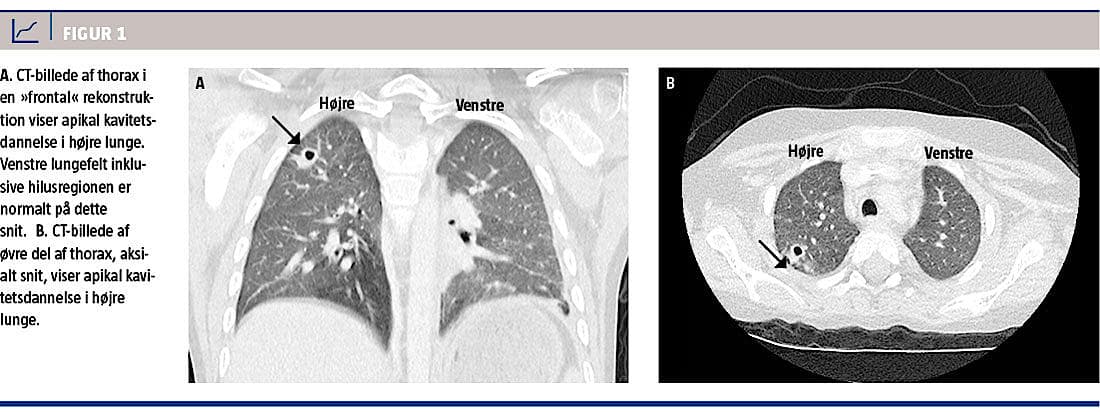

Hos patienter med specifikke eller uspecifikke symptomer på pneumoni og samtidig tilstedeværelse af rundinfiltrater med eller uden kavitetsdannelse påvist ved røntgenundersøgelse af lungerne, er Nocardia-infektion en sjælden, men vigtig differentialdiagnose. CT af lungerne viser ofte flere rundinfiltrater af forskellig størrelse. Infiltraterne kan være uskarpt afgrænsede og kan have kavitetsdannelse (Figur 1) [2]. Diagnosen stilles ved mikroskopi og aerob dyrkning. Prognosen er afhængig af patientens immunstatus, sygdommens varighed og evt. spredning – f.eks. hæmatogent til centralnervesystemet [3].